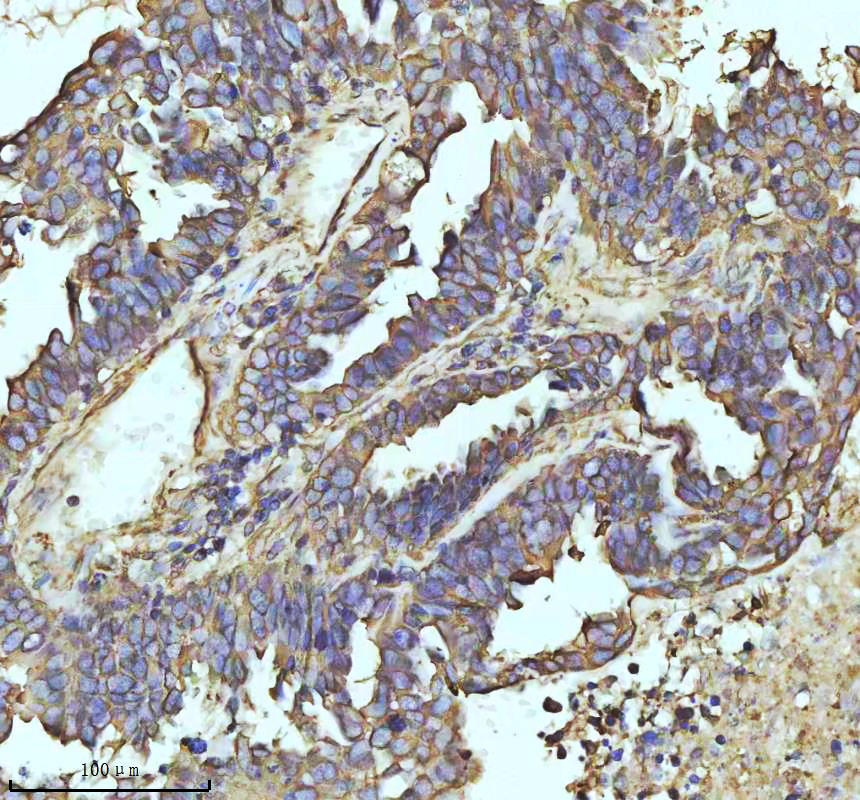

IHC analysis of beta I Tubulin/TUBB1 using anti-beta I Tubulin/TUBB1 antibody (BM3878) .

beta I Tubulin/TUBB1 was detected in a paraffin-embedded section of human ovarian cancer tissue. The tissue section was incubated with rabbit anti-beta I Tubulin/TUBB1 Antibody (BM3878) at a dilution of 1:200 and developed using HRP Conjugated Rabbit IgG Super Vision Assay Kit (Catalog # SV0002) with DAB (Catalog # AR1027) as the chromogen.